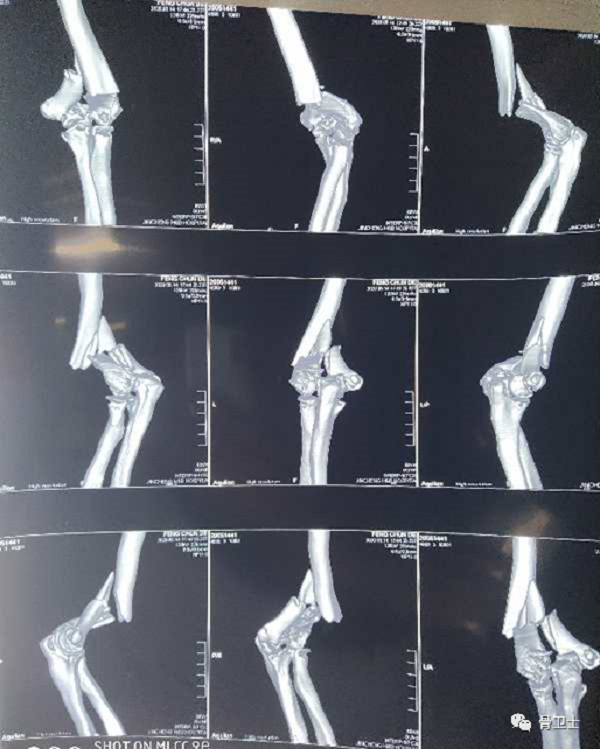

影像检查:左肘关节DR、CT示左肱骨远端粉碎性骨折

6.png

7.png